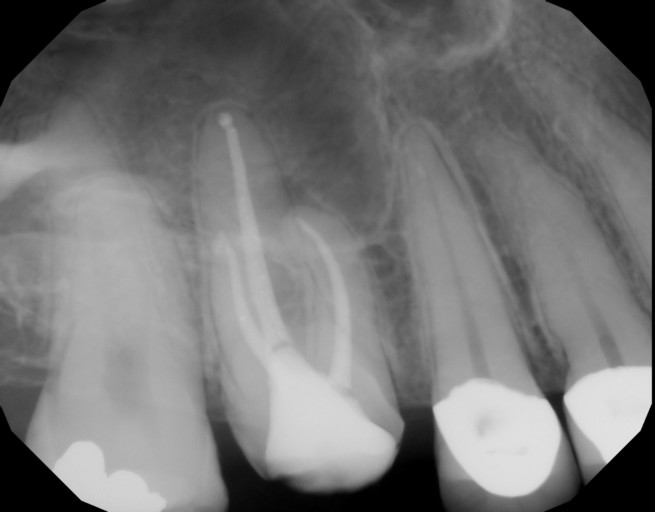

Root canal re-treatment- periapical cyst

Hi, I had a root canal re-treatment due to a periapical cyst. I had no symptoms but decided to be proactive. The doctor opened the canal and drained it. A week later the doctor disinfected the canal and filled it in. He didn't use calcium hydroxide...